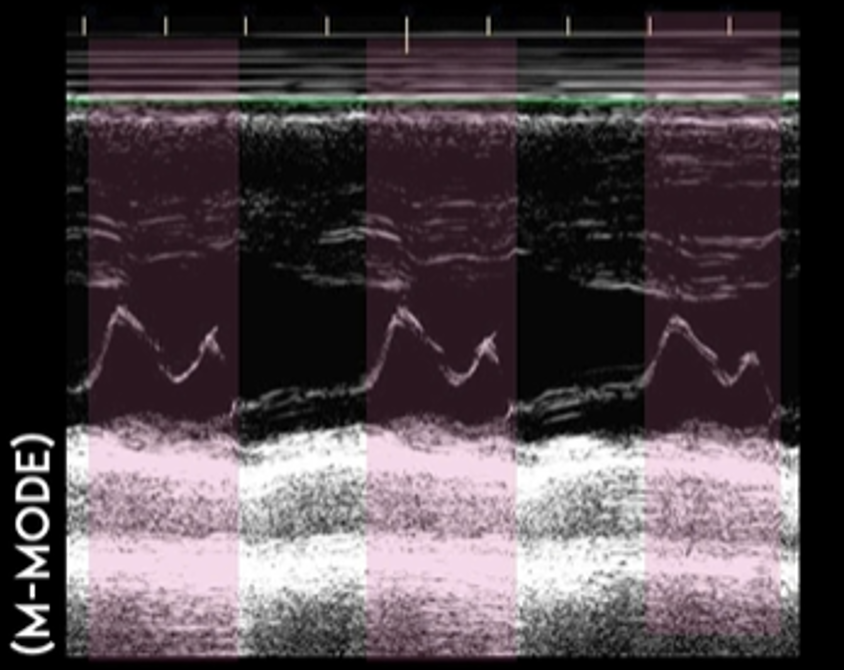

Finding #3: Systolic anterior motion (SAM) of mitral valve

View: PSL View with M Mode, place axis as if you were measuring EPSS at tip of mitral valve

• During systole, the mitral valve should be closed. But in HCM, the mitral valves actually move anteriorly during systole. This can be visualized by using M-Mode.

• This finding used to be pathognomonic for HCM but recent studies have found that only 25-50% of HCM patients with SAM have LVOTO

• The time the mitral valve is in contact with the septum can classify disease severity:

• Mild: brief SAM without septal contact

• Moderate: septal contact is < ⅓ of systolic period

• Severe: septal contact is > ⅓ of systolic period

• Notably, you will also see mitral regurgitation on ultrasound as well

This is the M Mode on the PSL View of a normal heart. Notice how you see the opening of the mitral valve in diastole (almost touches the septum) and the closing of the mitral valve in systole.